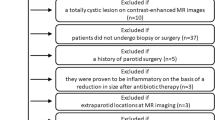

Our retrospective study was approved by the institutional review board in our hospital, with informed consent waived due to the retrospective nature of this study. Potentially eligible patients with histologically confirmed PTs between August 2016 and October 2019 were identified. Inclusion criteria were the following: (1) patients who underwent both DCE-MRI and RESOLVE-DWI; (2) tumors with maximum diameter > 1 cm; (3) enough noncystic/nonnecrotic areas within the tumors for imaging analysis; and (4) good quality of MR images without severe motion or susceptibility artifacts. Patients with presence of cyst (i.e., branchial cleft cyst and lymphoepithelial cyst), lipomyoma, or lymphangioma reliably diagnosed by clinical and radiological methods and patients who had biopsy or surgery less than 2 weeks before MR examination were excluded from the study. Finally, a total of 123 patients (mean age, 49.2 years; age range, 16–78 years) with 145 histologically proven PTs including 51 tumors with PAs, 52 tumors with WTs, 15 tumors with MTs, and 27 tumors with OBNs were enrolled in this study. The MTs included mucoepidermoid carcinoma (n = 6), acinar cell carcinoma (n = 2), duct carcinoma (n = 2), lymphoma (n = 2), carcinoma ex pleomorphic adenoma (n = 1), mammary analogue secretory carcinoma (n = 1), and fibrosarcoma (n = 1). Other benign tumors included basal cell adenoma (n = 18), schwannoma (n = 5), oncocytoma (n = 1), cystadenoma (n = 1), myoepithelioma (n = 1), and hemolymphangioma (n = 1).